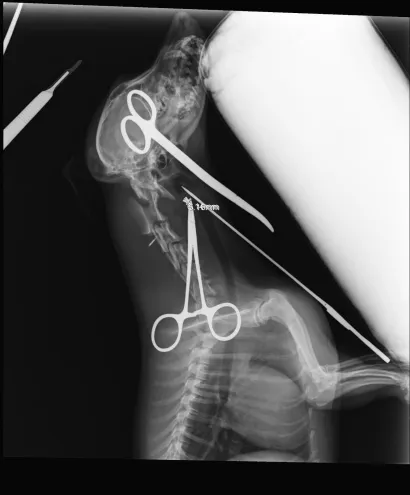

Maleni pas mješanac pogođen je dijabolom u vrat, a budući da je metak ostao smješten na nezgodnom mjestu blizu kralježnice, veterinar Mate Karaula iz Daruvara koji liječi Lenu, odustao je od vađenja metka zbog daljnjeg rizika po kujicu.

Prema nalazu veterinara dr. Mate Karaule, rendgenska snimka pokazala je da se metak, točnije dijabola, nalazi u području između atlasa i aksisa – dijela vratne kralježnice.

- Veličina projektila procijenjena je na 6,10 do 5,16 milimetara, a zbog dubine položaja i blizine kralježnice procijenjeno je da bi pokušaj vađenja mogao izazvati ozbiljne komplikacije. Zbog toga se odustalo od kirurškog vađenja metka.

Pas je primio injekcijsku sedaciju, obavljene su dvije rendgenske snimke i kirurška obrada rane, kazao nam je dr. Karaula.